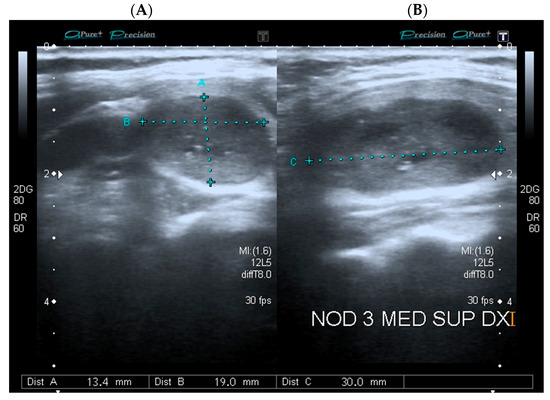

| AP diameter, mm | 17 (12.5–24.7) | 13.3 (10.0–20.9) | <0.001 |

| LL diameter, mm | 22.5 (16.2–32.0) | 15.6 (11.6–24.3) | <0.001 |

| L diameter, mm | 26.3 (19.0–35.8) | 18.4 (12.7–28.1) | <0.001 |

| Max diameter, mm | 26.3 (19.3–36.8) | 18.5 (12.6–28.2) | <0.001 |

| L diameter-AP diameter > 5 mm | 0.386 (0.197–0.754) | 0.005 | |

| L diameter-AP diameter > 5 mm | 0.467 (0.175–1.248) | 0.129 | |

| L diameter-AP diameter > 5 mm | 0.315 (0.125–0.795) | 0.014 | |

| L diameter-AP diameter ≤ 5 mm a | 59.6 | 70.2 | 52.8 | 75.6 | 66.4 (61.5–71.0) |

| L diameter-AP diameter ≤ 5 mm b | 53.1 | 69.7 | 38.8 | 80.3 | 65.2 (57.9–72.1) |

| L diameter-AP diameter ≤ 5 mm c | 54.6 | 64.1 | 34.3 | 80.4 | 61.6 (50.5–71.9) |

| L diameter-AP diameter ≤ 5 mm d | 51.9 | 74.7 | 43.8 | 80.3 | 68.4 (58.2–77.4) |